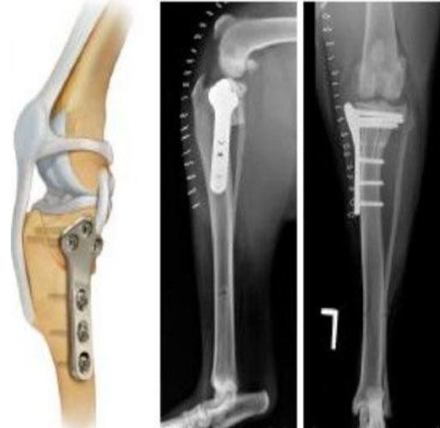

TPLO : Tibial Plateau Leveling Osteotomy

강아지 후지파행의 한 원인인 전십자인대 단열의 경우에 시행하는 수술로서 최근 낭외재건술보다 우선 선택되는 수술법입니다.